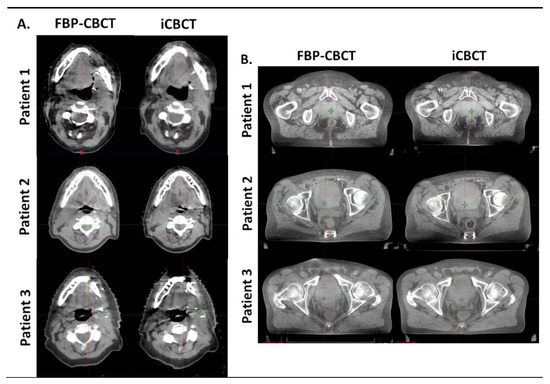

3.4. Patients